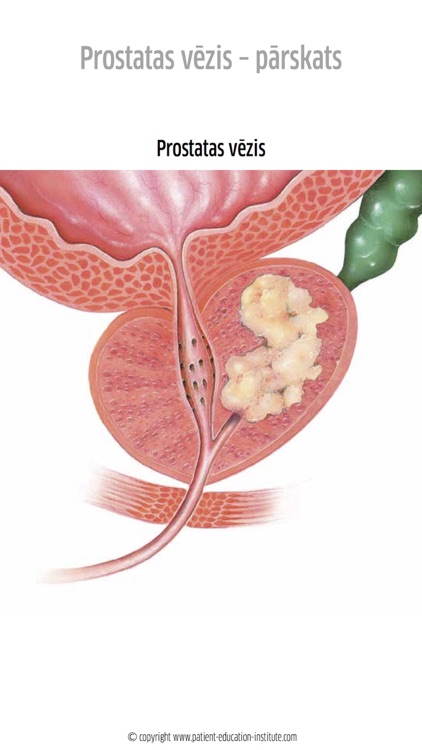

Containing 100s of medical illustrations, the patient-education-institute app is a unique visual aid that helps health care professionals enhance the quality of conversations with their patients. Each clinical situation is presented in a well-structured manner with simple illustrations, icons and short supporting texts.

Containing 100s of medical illustrations, the patient-education-institute app is a unique visual aid that helps health care professionals enhance the quality of conversations with their patients. Each clinical situation is presented in a well-structured manner with simple illustrations, icons and short supporting texts.

Simplicity and Structure

To every patient a consult is a very stressful situation in which his/her capability to absorb information is very limited. That's why our materials excel in presenting each clinical situation as simply as possible, with plenty of high-quality yet simple-to-understand illustrations that adequately support your explanation but leave out any unnecessary complications.